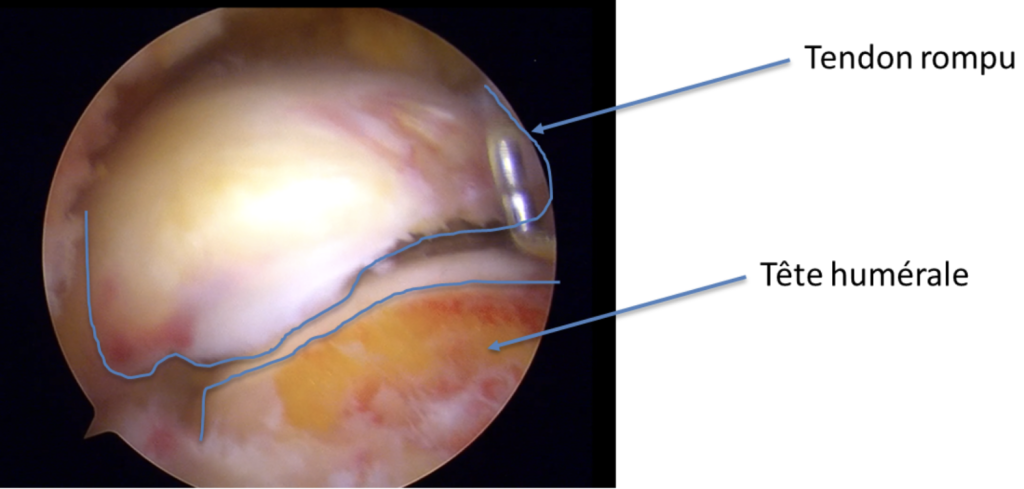

Visualisation de la rupture du tendon

Le tendon le plus fréquemment touché est le tendon supra épineux.

La rupture de la coiffe des rotateurs se réfère à une lésion touchant un ou plusieurs tendons au niveau de l’épaule. La coiffe des rotateurs est constituée de quatre tendons – le petit rond, le sous-épineux, le sus-épineux et le sous-scapulaire – qui recouvrent la tête de l’os du bras (humérus). Ces tendons jouent un rôle crucial dans la mobilité de l’épaule, notamment dans les mouvements d’élévation et de rotation.